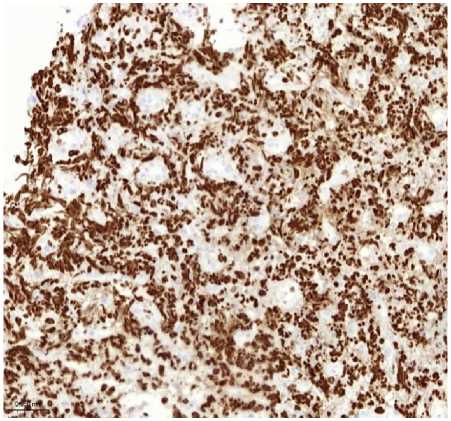

Рисунок 1. Плазмобластная лимфома. Биопсия кожи. Визуализируются клетки среднего размера с крупным ядром и заметными ядрышками. А. Окраска гематоксилином и эозином, увеличение ×200. Б. Иммуногистохимическое исследование с антителом CD138, увеличение ×200. В. Иммуногистохимическое исследование с антителом CD20, увеличение ×200. Г. SISH исследование к EBV, увеличение ×200. Д. Иммуногистохимическое исследование с антителом Ki67, увеличение ×200

Figure 1. Plasmoblastic lymphoma. Skin biopsy. Medium-sized cells with a large nucleus and prominent nucleoli are visualized. A. Hematoxylin and eosin staining, magnification ×200. Б. Immunohistochemical study with CD138 antibody, magnification ×200. В. Immunohistochemical study with CD20 antibody, magnification ×200. Г. SISH study for EBV, magnification ×200. Д. Immunohistochemical study with Ki67 antibody, magnification ×200

Гистологическое исследование: выявлен диффузный инфильтрат из крупных атипичных клеток с плазмобластным и иммунобластным фенотипом, ядрами неправильной формы, выраженным ядрышком и обильной базофильной цитоплазмой. Отмечались многочисленные фигуры митоза и обширные участки некроза.

Иммуногистохимическое исследование (ИГХ): Опухолевые клетки экспрессировали CD138, CD38, MUM1/IRF4; EBER (ISH) - положительно. Отмечалась негативная экспрессия CD20, PAX5, CD3. Индекс пролиферации Ki-67 >90%.

На основании данных морфологии и ИГХ был установлен диагноз: плазмобластная лимфома.